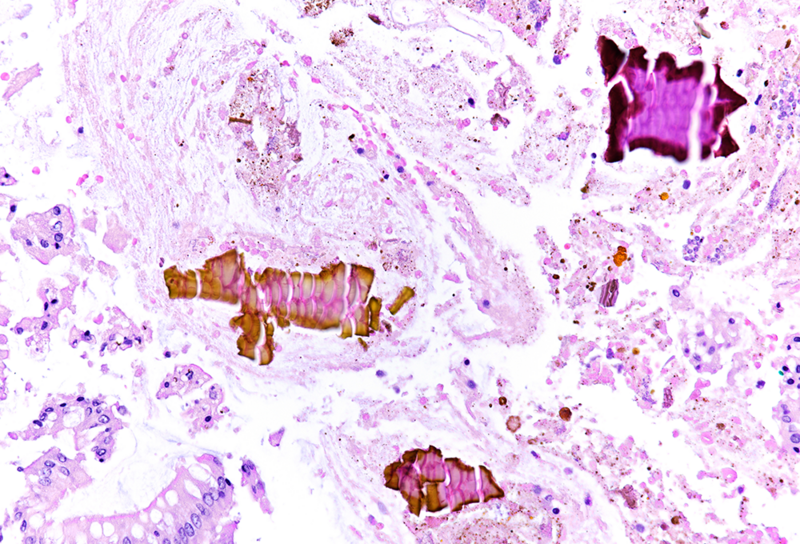

On macroscopy, multiple ulcers were visible on the mucosa of the colon. Histology showed ulcers with prominent granulation tissue, reaching the muscular wall of the bowel. They were surrounded by colonic mucosa with regenerative architectural changes (Panels A-B). In the ulcers and on the surface mucosa, yellow-pink polygonal foreign material with scale-like appearance was seen, which corresponded to the given sevelamer drug (Panels C-D).